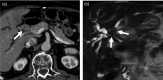

IgG4-related sclerosing cholangitis (IgG4-SC) is a distinct type of cholangitis frequently associated with autoimmune pancreatitis and currently recognized as a biliary manifestation of IgG4-related disease. Although clinical diagnostic criteria of IgG4-SC were established in 2012, differential diagnosis from primary sclerosing cholangitis and cholangiocarcinoma is sometimes difficult. Furthermore, no practical guidelines for IgG4-SC are available. Because the evidence level of most articles retrieved through searching the PubMed, Cochrane Library, and Igaku Chuo Zasshi databases was below C based on the systematic review evaluation system of clinical practice guidelines MINDS 2014, we developed consensus guidelines using the modified Delphi approach. Three committees (a guideline creating committee, an expert panelist committee for rating statements according to the modified Delphi method, and an evaluating committee) were organized. Eighteen clinical questions (CQs) with clinical statements were developed regarding diagnosis (14 CQs) and treatment (4 CQs). Recommendation levels for clinical statements were set using the modified Delphi approach. The guidelines explain methods for accurate diagnosis, and safe and appropriate treatment of IgG4-SC.